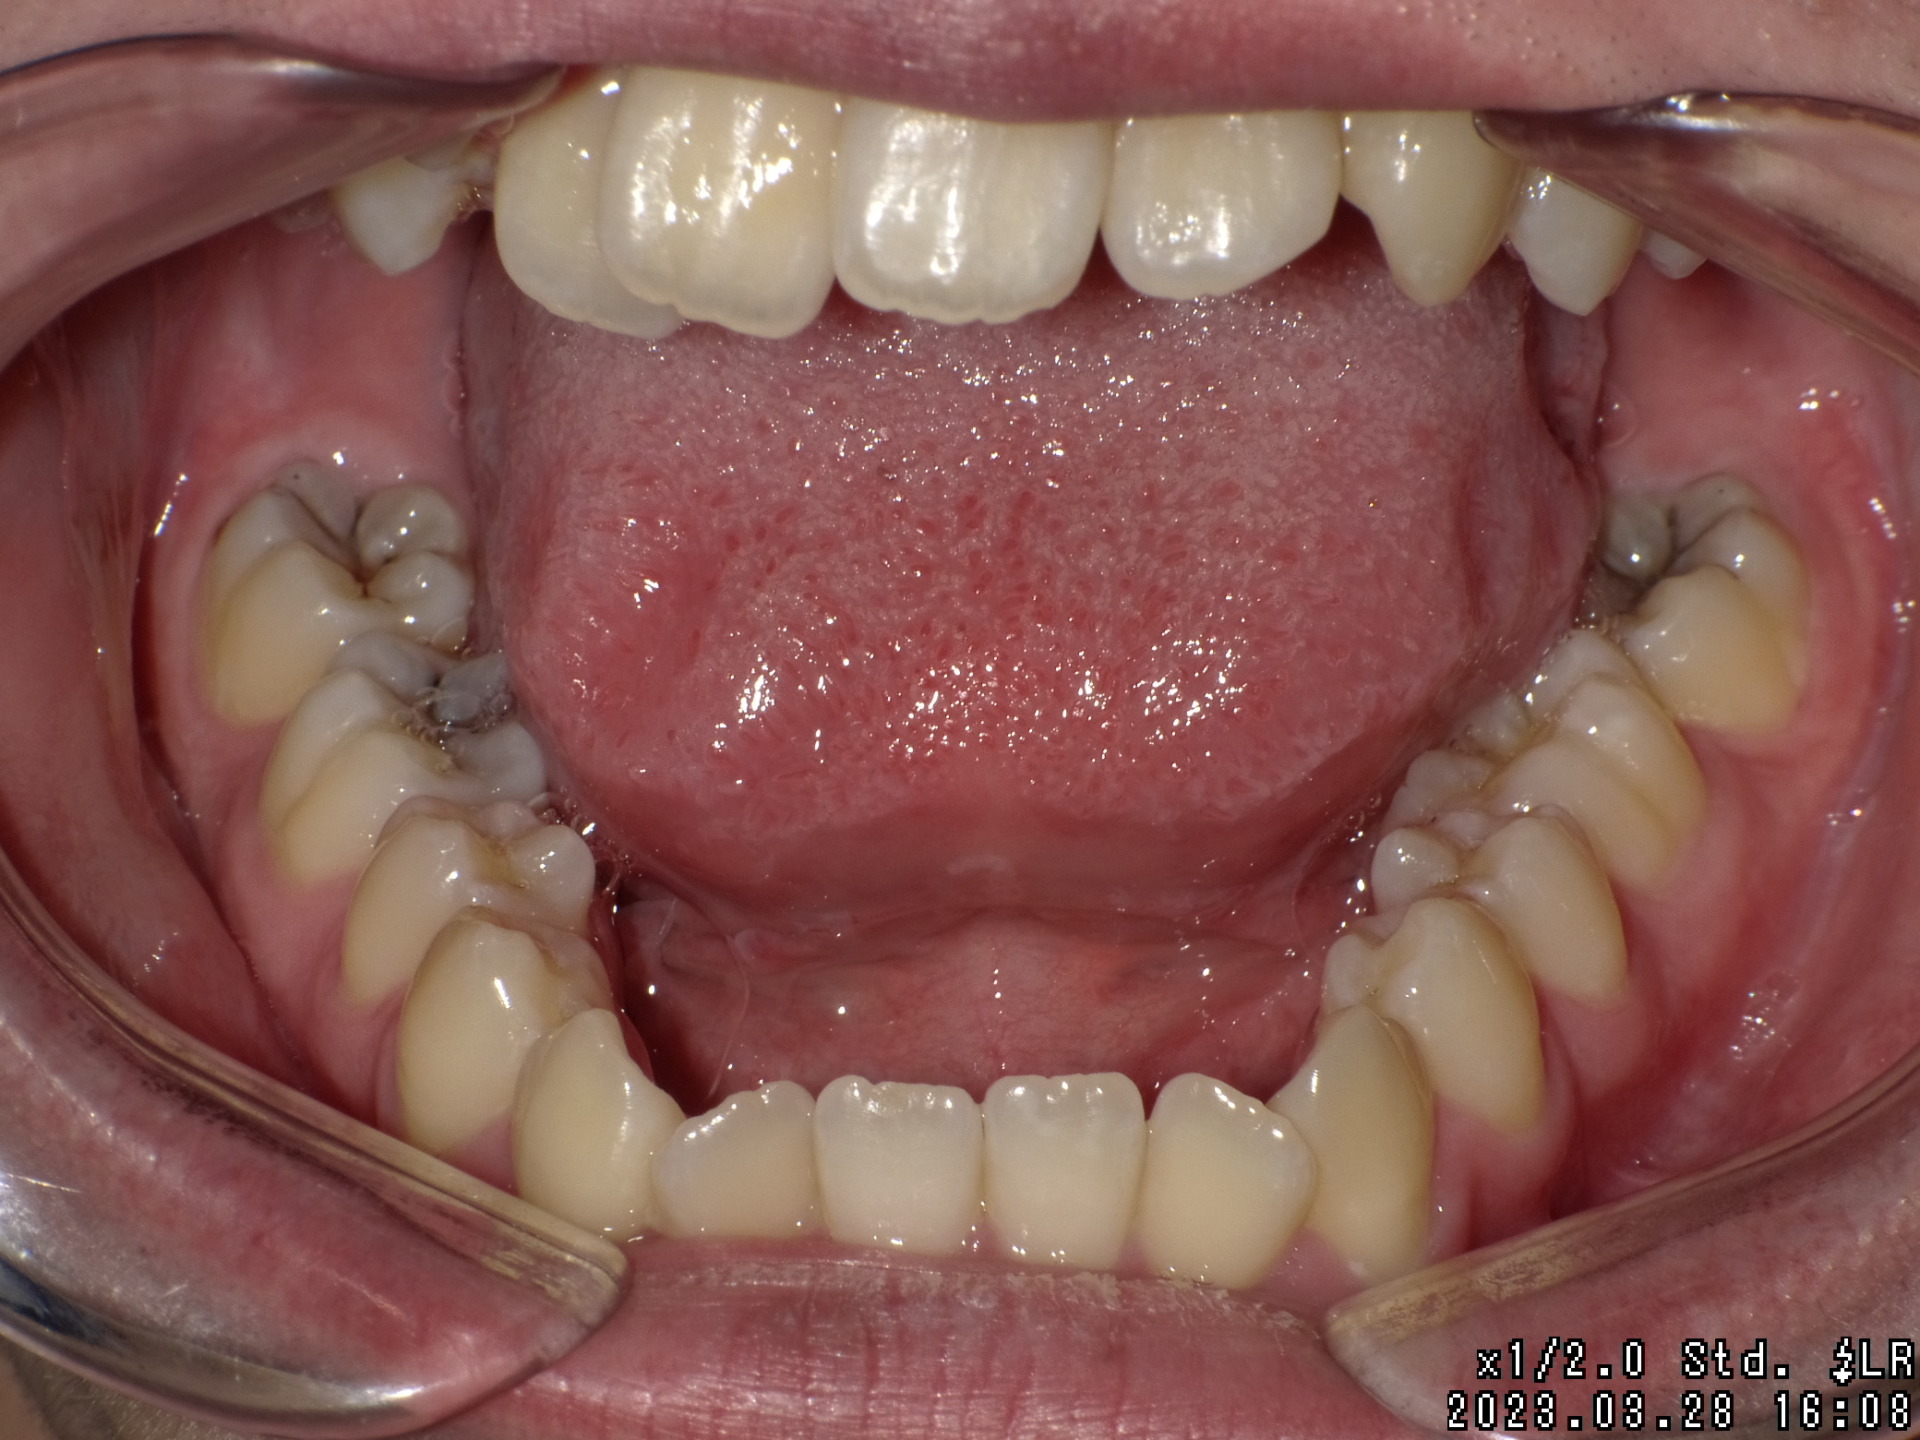

Before